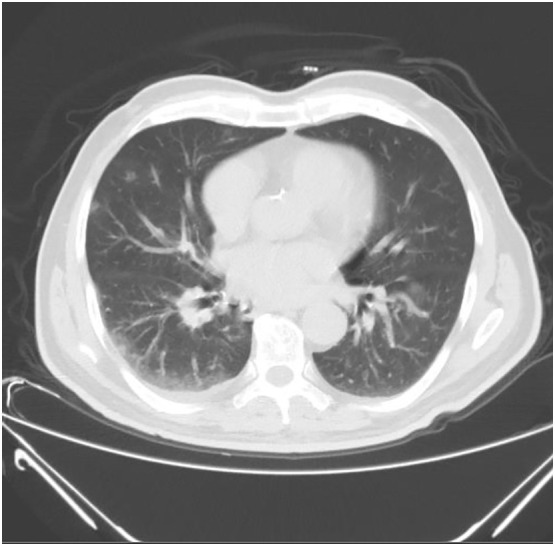

A 72-year-old male patient was brought to the emergency room with complaints of altered consciousness, retardation in movements, and tremors. It was learned that the patient, who was previously known to have diabetes mellitus, hypertension and peripheral artery disease, was diagnosed with COVID-19 confirmed by Real-Time-Polymerase-Chain-Reaction in the hospital where he applied with sore throat and fever 2 days ago. Paracetamol and favipiravir were started on the patient, and his fever subsided the next day. On the 3rd day of the diagnosis of COVID-19, it was learned that the patient was observed to have dull gaze not answering the questions asked, impaired walking and tremors and that the emergency call system was notified. The patient's blood pressure was 130/80 mmHg, fever was 36.5 degrees, respiratory rate was 22 and saturation was 92%. In the neurological examination, he was conscious, but he did not sense the deixis referring to place, time and person. Asymmetry was not detected in the examination of muscle strength, sensory, cerebellar and head pair. In the tonus examination, it was observed that he had rigidity and cogwheel rigidity. His movements were bradykinetic. His gait was in an antiflexion position and was slowed down. He had a rest tremor. He had rales in the right lung basal. He had no history of drug intake that caused parkinsonism. No acute pathology was detected in his brain tomography and diffusion-weighted magnetic resonance imaging. Increases, due to Covid pneumonia, in bilateral ground glass density of the patient, whose thoracic tomography taken on the day of diagnosis was normal, were observed in the thoracic CT taken at the time of admission to the hospital (Fig. 1 ). Routine biochemical tests were normal in laboratory tests, CRP 13.2 m / dl, ferritin 67μgr/L, D-dimer 0.7 mg/L, Fibrinogen 493 g/L, lymphocyte 1.331033/mm3, platelet 1021033/mm3. On the day of hospitalization, 1 unit of convalescent plasma treatment was administered. Approximately 4 h after the administration of the conventional treatment, it was noticed that his orientation and cooperation improved and his rigidity decreased. In the following day evaluation, the patient was consciously oriented and cooperative, and his rigidity, tremors and bradykinesia disappeared. However, the lymphocyte count fell to 0.721033/mm3. Other tests were normal. As respiratory distress increased, 1more unit convalescent plasma treatment was given, high-flow nasal cannula and noninvasive mechanical ventilation were initiated. On the 5th day saturation decreased (Fig. 2 ), lymphocyte decreased to 0.411033/mm3, platelet to 701033/mm3, Ferritin increased to 309.7 μgr/L, Fibrinogen 918 g/L, CRP 271 mg/L. Plasmapheresis treatment was decided to be applied to the patient who developed ARDS. After 3 days of plasmapheresis, the patient's oxygen saturation improved, respiratory distress decreased, and he was transferred to the service. The patient, who was followed up in the intensive care unit for 14 days and in the ward for 8 days, was discharged with full recovery. His neurological examination in the follow-up 2 months was found normal. Symptoms and signs of parkinsonism were not observed.

Fig. 1.

Tomography image of the patient at admission (3th day).